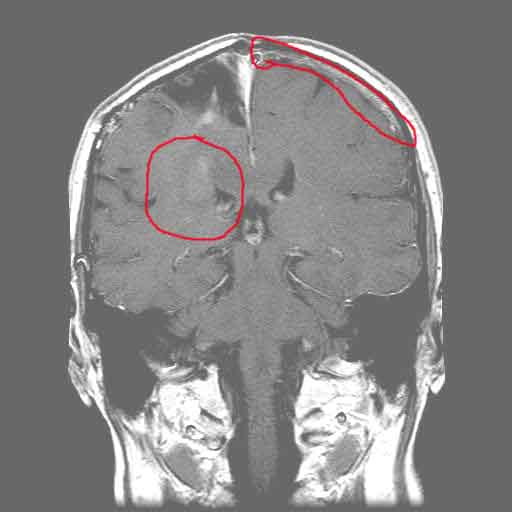

As we have known since January, my tumor is regrowing.  I had a short break where the Temodar seemed to be making some difference.  But, even the Temodar seems to be failing now.  I got an MRI last week showing a new mass deep in the white matter of the parietal lobe.  I have known for some time that I have been getting worse and worse.  I asked Abi “What’s different today than yesterday?”  And she said “Now we have radiological confirmation that the tumor is regrowing.”  And the kicker is, that there is no additional treatment for this type of tumor – in either Western or Eastern medicine.  Well, ok, there are treatments I could try, with known severe side effects, and very minimal effectiveness.  Maybe adding 6 or 9 months to my life, if they work.